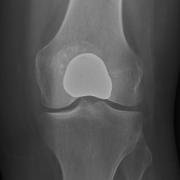

Hemicap patellofemoral replacement from the front.

A metal component replaces the damaged trochlear groove of the femur, and a plastic button replaces the rear patellar surface which is cut away to accommodate the implant.

The trochlear implant is comprised of metal and shows up as white. The plastic patellar component is showing only as a space between the trochlear implant and the remainder of the patella.